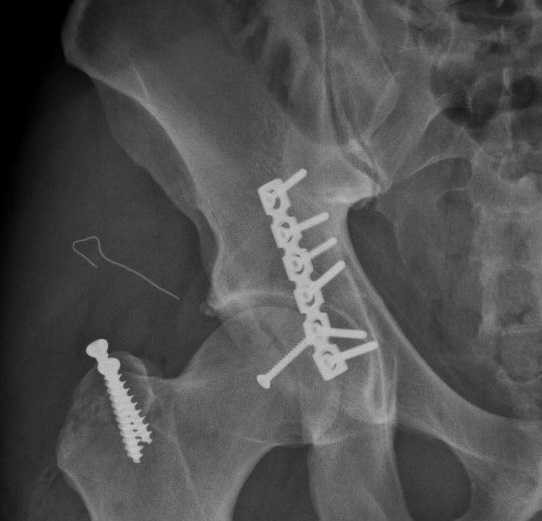

Các bác sĩ Vinmec đã mổ nắn trật khớp, đồng thời kết xương bằng nẹp vít ổ cối để xử trí tai nạn trật khớp háng cho anh Dustin

Chấn thương của anh Dustin khá hiếm gặp, vùng tổn thương ở sâu, vi trường phẫu thuật hạn chế, xung quanh các mảnh vỡ là dây thần kinh và mạch máu quan trọng. Với ca chấn thương này, TS Nghĩa và các bác sĩ Vinmec đã tiến hành nắn trật khớp trở lại, đồng thời kết xương bằng nẹp vít ổ cối thành công cho người bệnh trong ca mổ kéo dài hơn 4 tiếng. 3 ngày sau mổ, Dustin đã bắt đầu tập đi. Và 6 ngày sau, anh đã được ra viện, đồng thời định kỳ đến tập phục hồi chức năng theo các bài tập chuyên sâu tại bệnh viện.